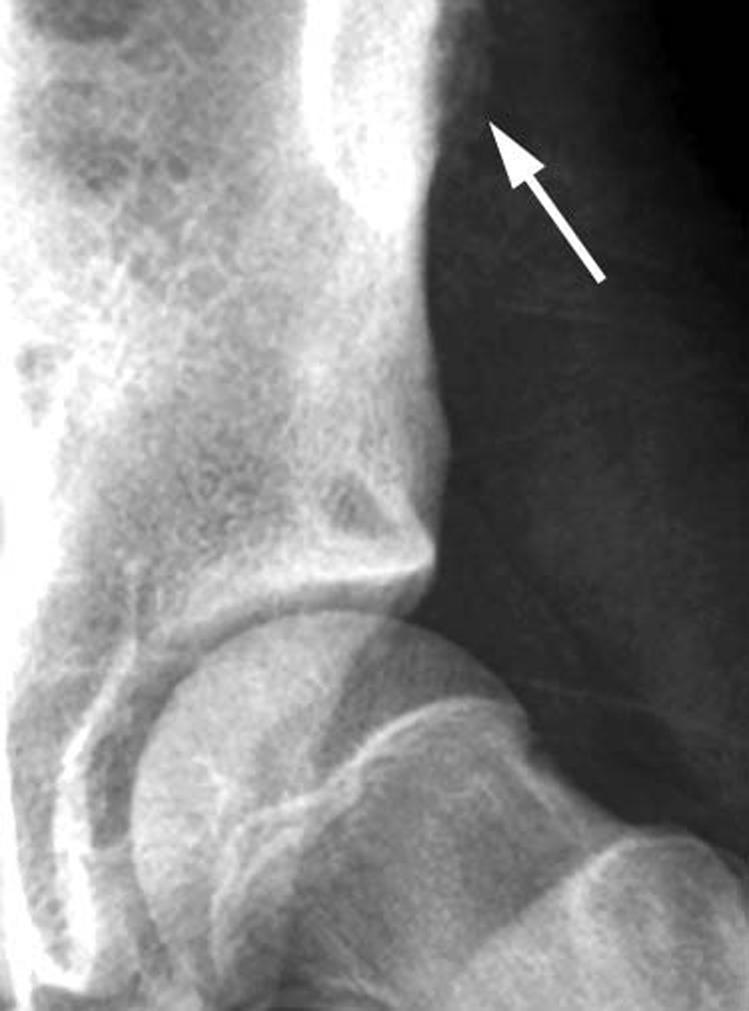

Orthopaedic magnetic resonance imaging challenge: apophyseal avulsions at the pelvis.

Apophyseal avulsion injuries of the hip and pelvis are frequent athletic injuries in children and adolescents, most commonly associated with explosive movement or sprinting. This article details typically encountered apophyseal injuries and their appearance on magnetic resonance imaging.